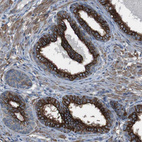

Immunohistochemical staining of human pancreas shows strong membranous and cytoplasmic positivity in exocrine glandular cells.